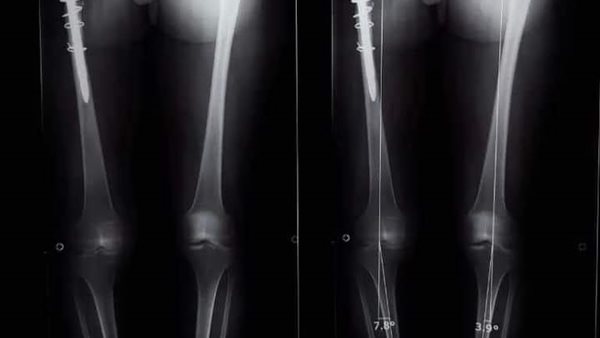

وأوضح الدكتور عمرو السيد علي أستاذ جراحة العظام، واستشاري الجراحات الميكروسكوبية بجامعة أسيوط ، أن المريضة تبلغ من العمر 15 عامًا ، وكانت تعاني من وجود ورم في عظمة الآلية، ومفصل الحوض؛ مشيرًا إلى إجراء العملية الجراحية على مرحلتين في إطار زمني 3 شهور ؛ لتجنب البتر؛ حيث تم في المرحلة الأولي إزالة الورم من عظمة الآلية، ونقل الجزء العلوي من عظمة الفخذ ؛ لتحل محل عظمة الآلية.

وأوضح الدكتور محمد مهران أستاذ جراحة العظام المساعد، واستشاري جراحات تغيير المفاصل الصناعية بجامعة أسيوط، أنه تم- بعد إجراء الفحوصات الطبية- تركيب مفصل صناعي كامل ذي مواصفات خاصة للحوض، وذلك دون اللجوء لتثبيت المفصل، ولتجنب البتر لهذا الطرف؛ مشيرًا إلى نجاح العملية، واستقرار الحالة الصحية للمريضة، وتمت متابعتها؛ لحين عودة حركة المريضة لصورتها الطبيعية، ومشيرا في الوقت نفسه، أنه تم نشر العملية الجراحية عالميًا: في مجلة علمية متخصصة للحالات الصعبة؛ بمساعدة الدكتور أحمد عادل خليفة مدرس جراحة العظام بكلية طب قنا- جامعة جنوب الوادي.